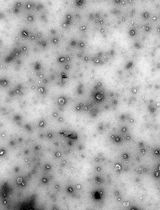

Lipid nanoparticles (LNPs) are powerful carriers for nucleic acid delivery, but plasmid DNA-loaded LNPs (pDNA-LNPs) have been limited by inflammation and toxicity. We showed that standard pDNA-LNPs activate the cGAS–STING pathway, leading to severe immune responses and mortality in mice. To overcome this, we co-loaded nitro-oleic acid (NOA), an endogenous STING inhibitor, into pDNA-LNPs. NOA-pDNA-LNPs mitigated inflammation, enabled safe in vivo delivery, and supported sustained gene expression for months. Here, we present a detailed protocol for producing and characterizing NOA-pDNA-LNPs to facilitate safer, long-term gene delivery applications.

The success of COVID-19 mRNA vaccines showcased the power of lipid nanoparticles (LNPs) to deliver nucleic acids and achieve high protein expression [1]. While most LNP applications focus on mRNA or siRNA, these cargos are short-lived and lack promoter control. In contrast, DNA offers longer-term expression (months to years), cell type–specific promoter regulation, and greater stability, making it ideal for expressing therapeutic proteins, gene editors, or shRNAs for long-term effects [2–4].

DNA-loaded LNPs combine durable expression with the advantages of LNPs: high delivery efficiency, low immunogenicity (compared to viral vectors), and flexible cargo capacity. However, their development has lagged due to safety concerns. We found that plasmid DNA-LNPs (pDNA-LNPs) trigger strong inflammation in naive mice, leading to 100% mortality at standard doses [5]. Using knockout mouse models and in vitro assays, we identified the cGAS–STING pathway as the main driver. This innate immune pathway detects cytosolic DNA and activates pro-inflammatory cytokines like type I interferons and IL-6.

To overcome this, we took inspiration from DNA viruses that evade STING-mediated immunity. We loaded pDNA-LNPs with nitro-oleic acid (NOA), an endogenous STING inhibitor. These NOA-pDNA-LNPs eliminated inflammation in vitro and prevented mortality in vivo, without compromising transgene expression.

Together, these results demonstrate that pDNA-LNPs co-loaded with bioactive lipids like NOA can enable safe, long-term gene expression. Here, we present a detailed protocol for producing NOA-pDNA-LNPs to support a broader application of this promising gene delivery platform.